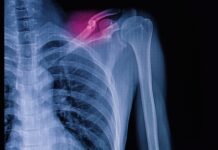

L’avvento di questi impianti ha però portato nuove evidenze radiografiche, in particolare con la formazione di radiolucenza periprotesica (PPRL), fenomeno che si vede soprattutto intorno alle tibie e al femore.

I pazienti – tutti sottoposti a follow-up a 6, 12 e 36 mesi dall’impianto – sono stati sottoposti a varie radiografie postoperatorie per verificare la presenza di PPRL, che è stata individuata in 29 impianti (23,8%).

Dal punto di vista della distribuzione, lo studio conferma la presenza soprattutto lungo la componente tibiale, seguita da quella femorale.